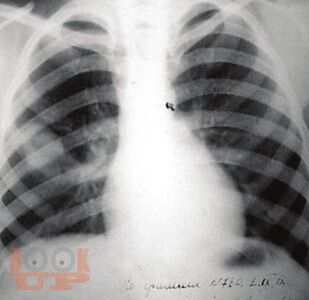

В учебно-методическом пособии представлены вопросы этиологии, патогенеза, патологической анатомии туберкулеза. Рассматриваются современные методы выявления туберкулеза органов дыхания и внелегочного туберкулеза. Отдельная глава посвящена вопросам клиники, диагностики туберкулеза полости рта. Освещены вопросы современного лечения и профилактики туберкулеза. Учебно-методическое пособие рекомендовано для студентов медицинских вузов, обучающихся по специальности «Стоматология» по дисциплине «Фтизиатрия». Изучение данного учебно-методического пособия способствует формированию у студентов следующих компетенций: ОПК-5, ОПК-6, ОПК-9, ПК-6, ПК-9.